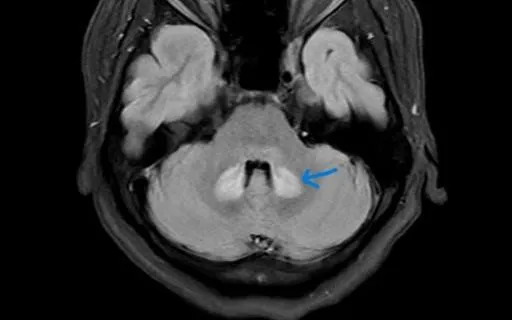

Khai thác bệnh sử cho thấy bệnh nhân có sử dụng sản phẩm lợi sữa trôi nổi trước đó. Kết quả chụp cộng hưởng từ (MRI) phát hiện tổn thương đối xứng tại cầu não, hành não và tiểu não - những vùng quan trọng của hệ thần kinh trung ương. Các bác sĩ nhận định đây là dấu hiệu cảnh báo nguy cơ ngộ độc thần kinh liên quan đến sản phẩm không rõ thành phần.